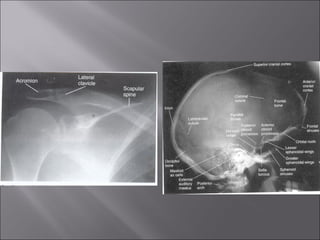

.Right (R) andleft marker for anatomical orientation Anatomical marker suitable for placing over the edge of a cassette to record on the film either the right or left.

 Torso, vertebral, cranial, shoulder, hipradiograph: as if the patient is standing in an upright position.